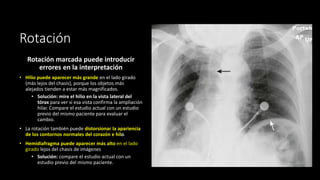

Rotación

Rotación marcada puede introducir

errores en la interpretación

• Hilio puede aparecer más grande en el lado girado

(más lejos del chasis), porque los objetos más

alejados tienden a estar más magnificados.

• Solución: mire el hilio en la vista lateral del

tórax para ver si esa vista confirma la ampliación

hilar. Compare el estudio actual con un estudio

previo del mismo paciente para evaluar el

cambio.

• La rotación también puede distorsionar la apariencia

de los contornos normales del corazón e hilo.

• Hemidiafragma puede aparecer más alto en el lado

girado lejos del chasis de imágenes

• Solución: compare el estudio actual con un

estudio previo del mismo paciente.